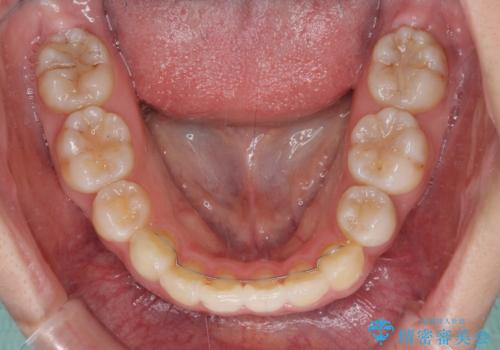

- 口元の突出感を気にして来院された患者様です。

診断の結果、上顎左右第一小臼歯4本抜歯により、叢生を解消するとともに口元を引っ込めていくことが望ましいと判断しました。

抜歯矯正による口元の改善にはワイヤー矯正が望ましいのですが、ダンサーとしての仕事を行っているため、インビザラインにて治療を行うこととしました。

インビザラインによる矯正治療は、どれだけマウスピースを外す時間を短くできるかが成功の鍵となりますが、抜歯矯正ではよりシビアに要求されます。

こちらの患者様は、1日22時間以上を厳守してくださり、3年強で終えることができました。